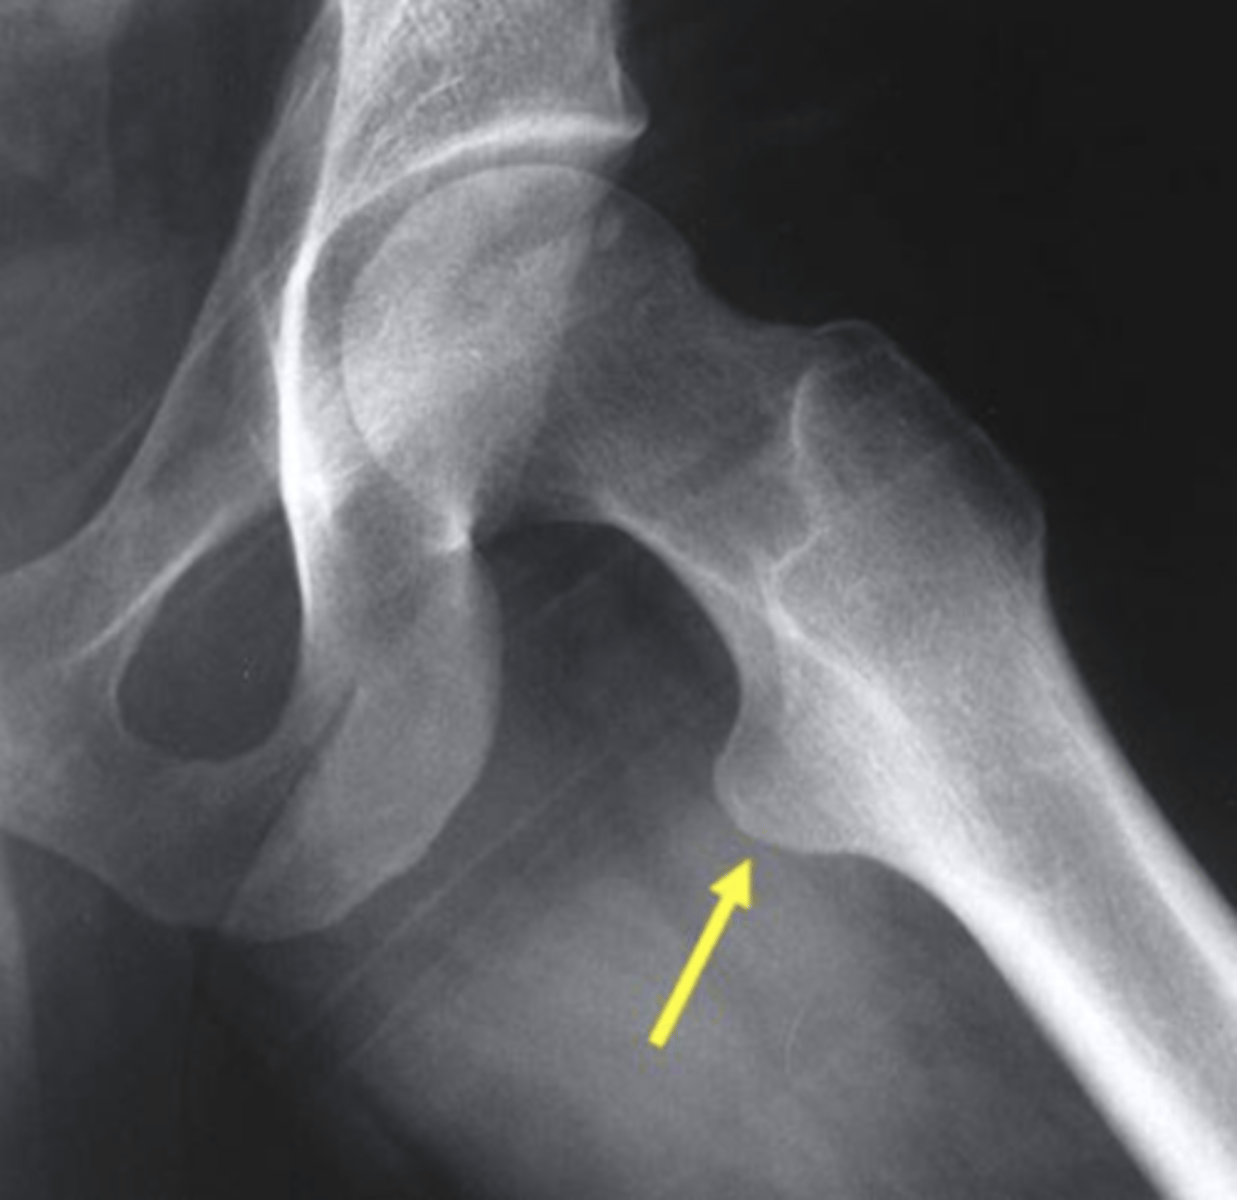

Which structure is highlighted by the yellow arrow in this frog leg lateral view of the hip?

lesser trochanter